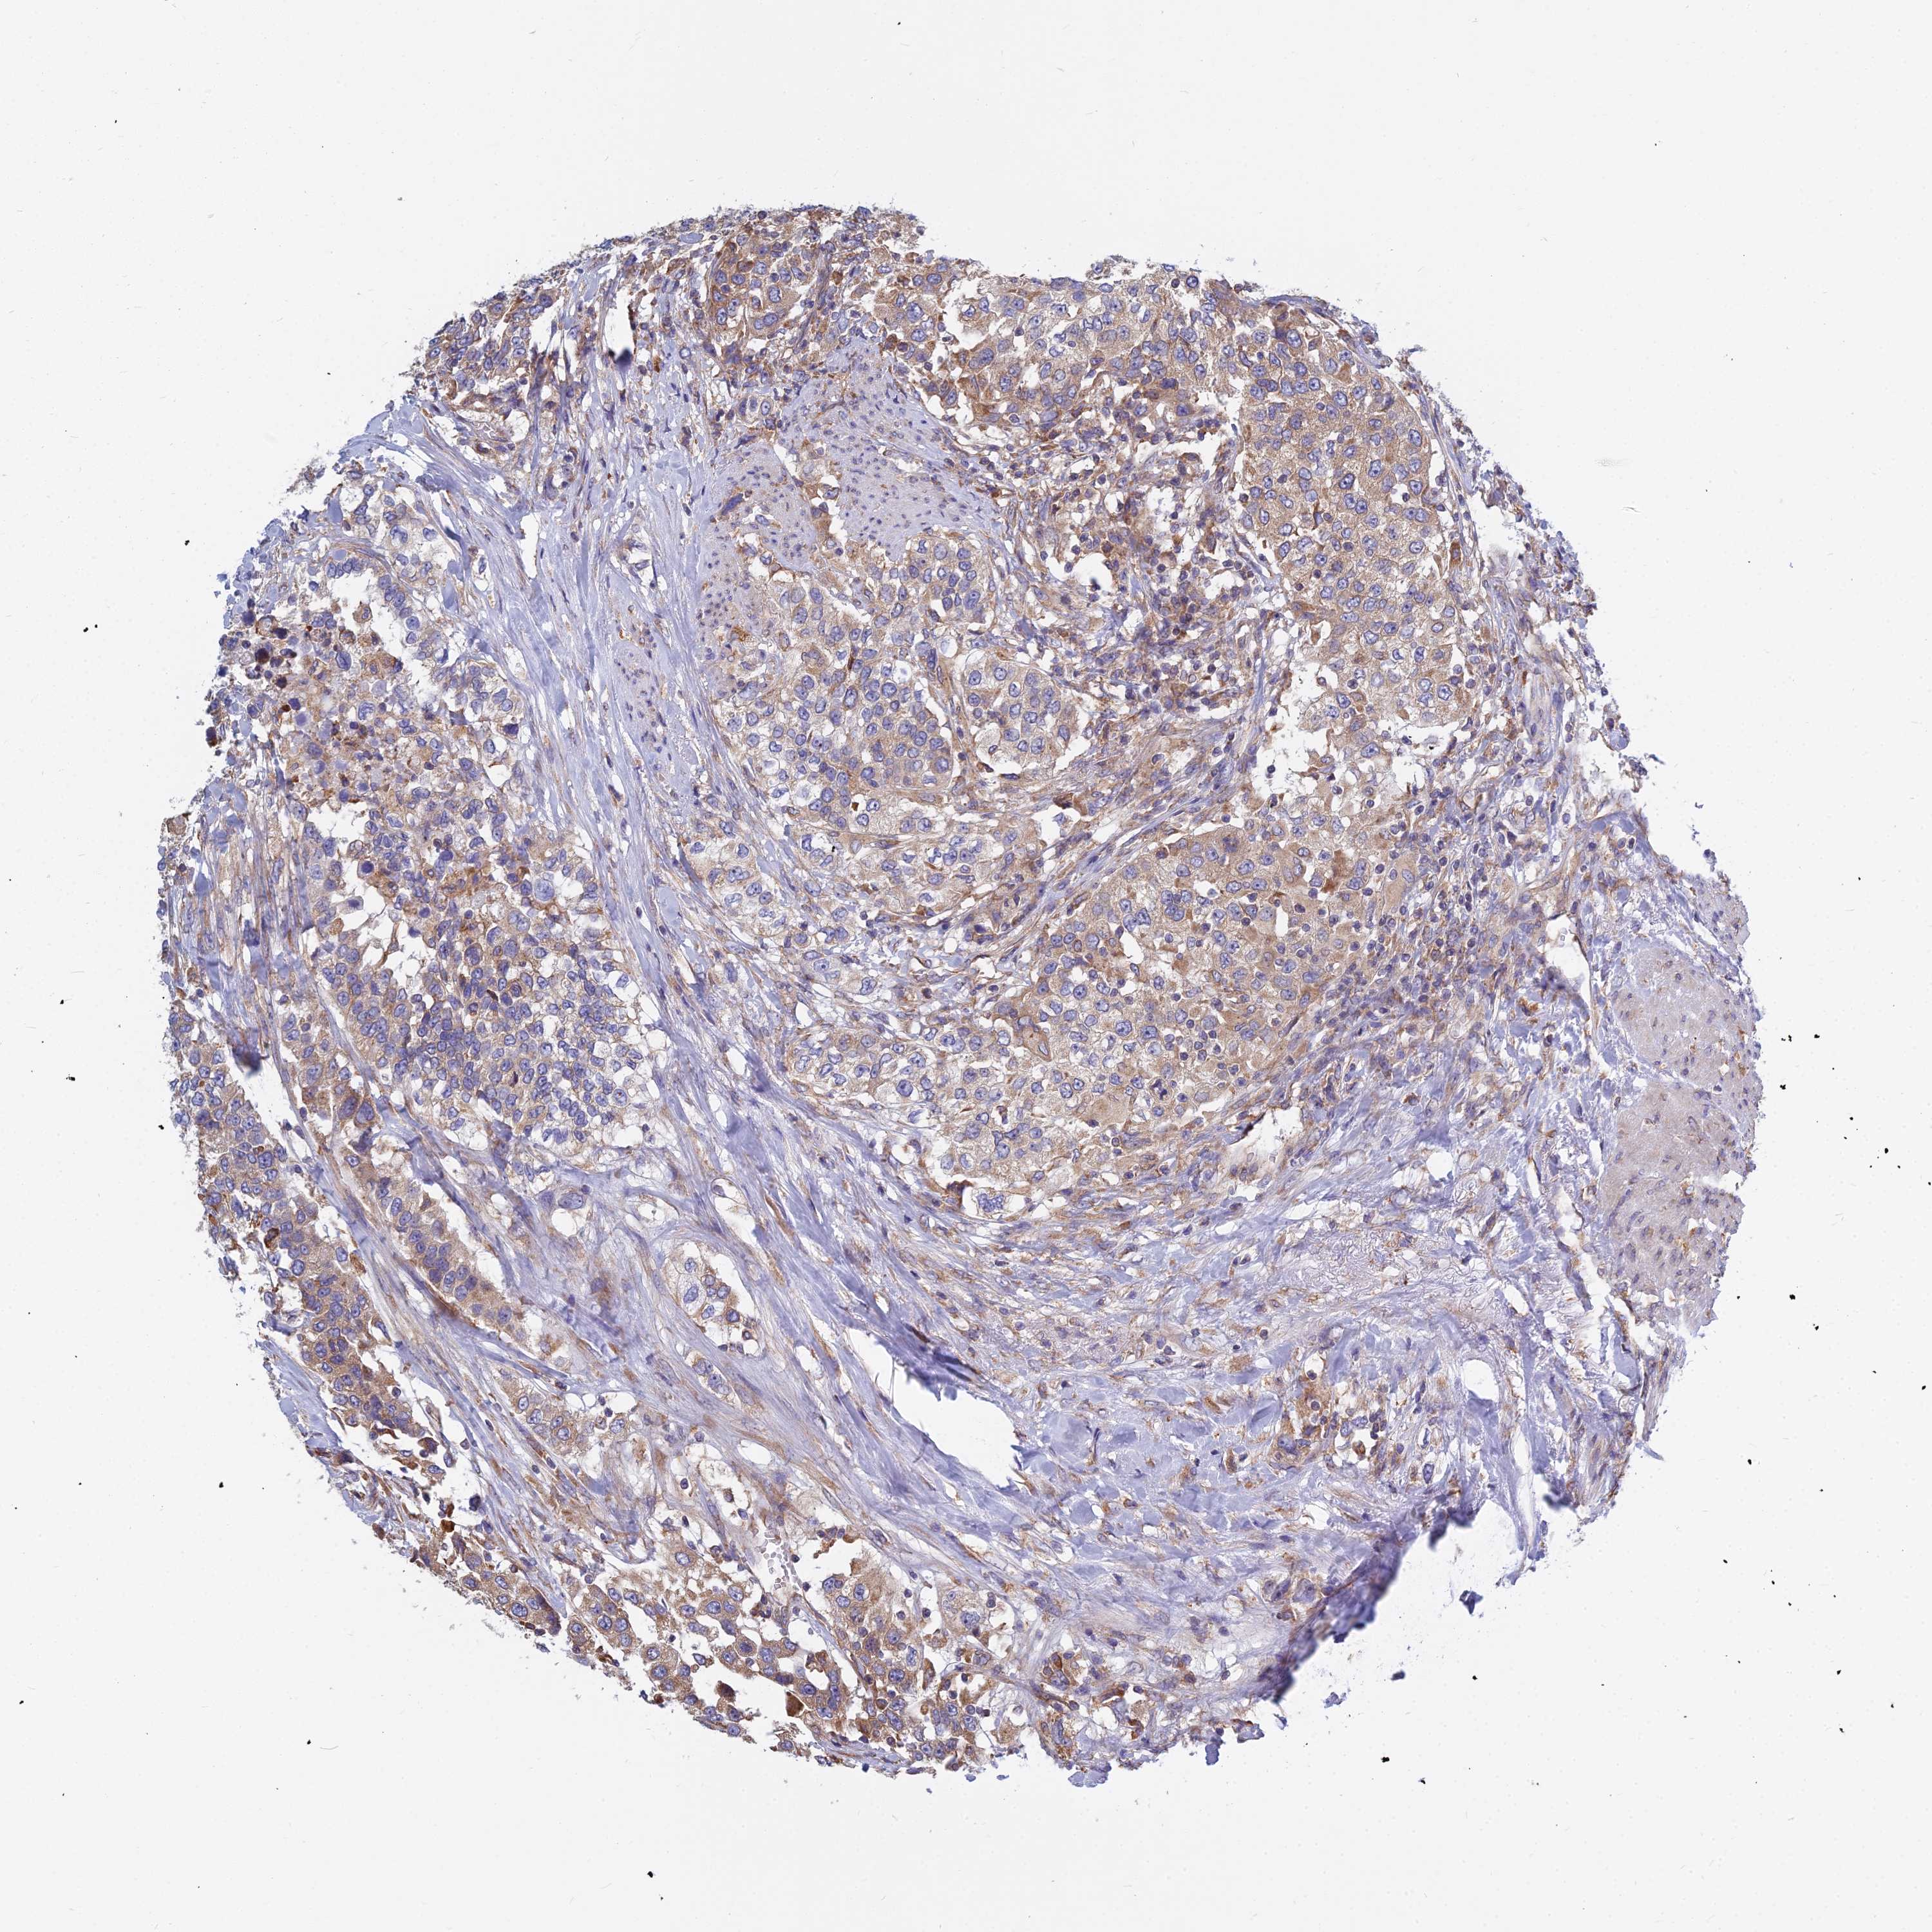

UROTHELIAL CANCER - Protein expressioni

A mouse-over function shows sample information and annotation data. Click on an image to view it in a full screen mode. Samples can be filtered based on level of antibody staining by selecting one or several of the following categories: high, medium, low and not detected. The assay and annotation is described here.

Note that samples used for immunohistochemistry by the Human Protein Atlas do not correspond to samples in the TCGA dataset.

Antibody stainingi

Antibody staining in the annotated cell types in the current human tissue is reported as not detected, low, medium, or high, based on conventional immunohistochemistry profiling in selected tissues. This score is based on the combination of the staining intensity and fraction of stained cells.

Each image is clickable and will lead to virtual microscopy that enables deeper exploration of all samples and also displays staining intensity scores, fraction scores and subcellular localization as well as patient and tissue information for each sample.

Antibody HPA045018

Staining

High

Medium

Low

Not detected

Intensity

Strong

Moderate

Weak

Negative

Quantity

>75%

75%-25%

<25%

None

Location

Nuclear

Cytoplasmic/membranous

Cytoplasmic/membranous,nuclear

Urothelial carcinoma, Low grade

Urothelial carcinoma, High grade